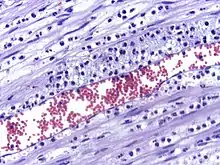

Micrograph showing leukocyte migration, H&E stain